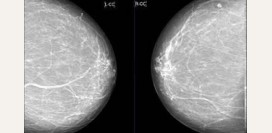

Упоминая тревожную статистику, добавим, что самоосмотр — это быстрый и весьма комфортный способ следить за здоровьем, который легко вписать в ритм жизни.

Потребуется:

- выбрать 5-7 день цикла,

- уделить 10 минут после душа,

- оценить грудь визуально перед зеркалом,

- проверить структуру и ткани на ощупь,

- покрутиться перед зеркалом, чтобы оценить форму и упругость,

- исключить выделения из сосков, если вы не кормите в данный момент.